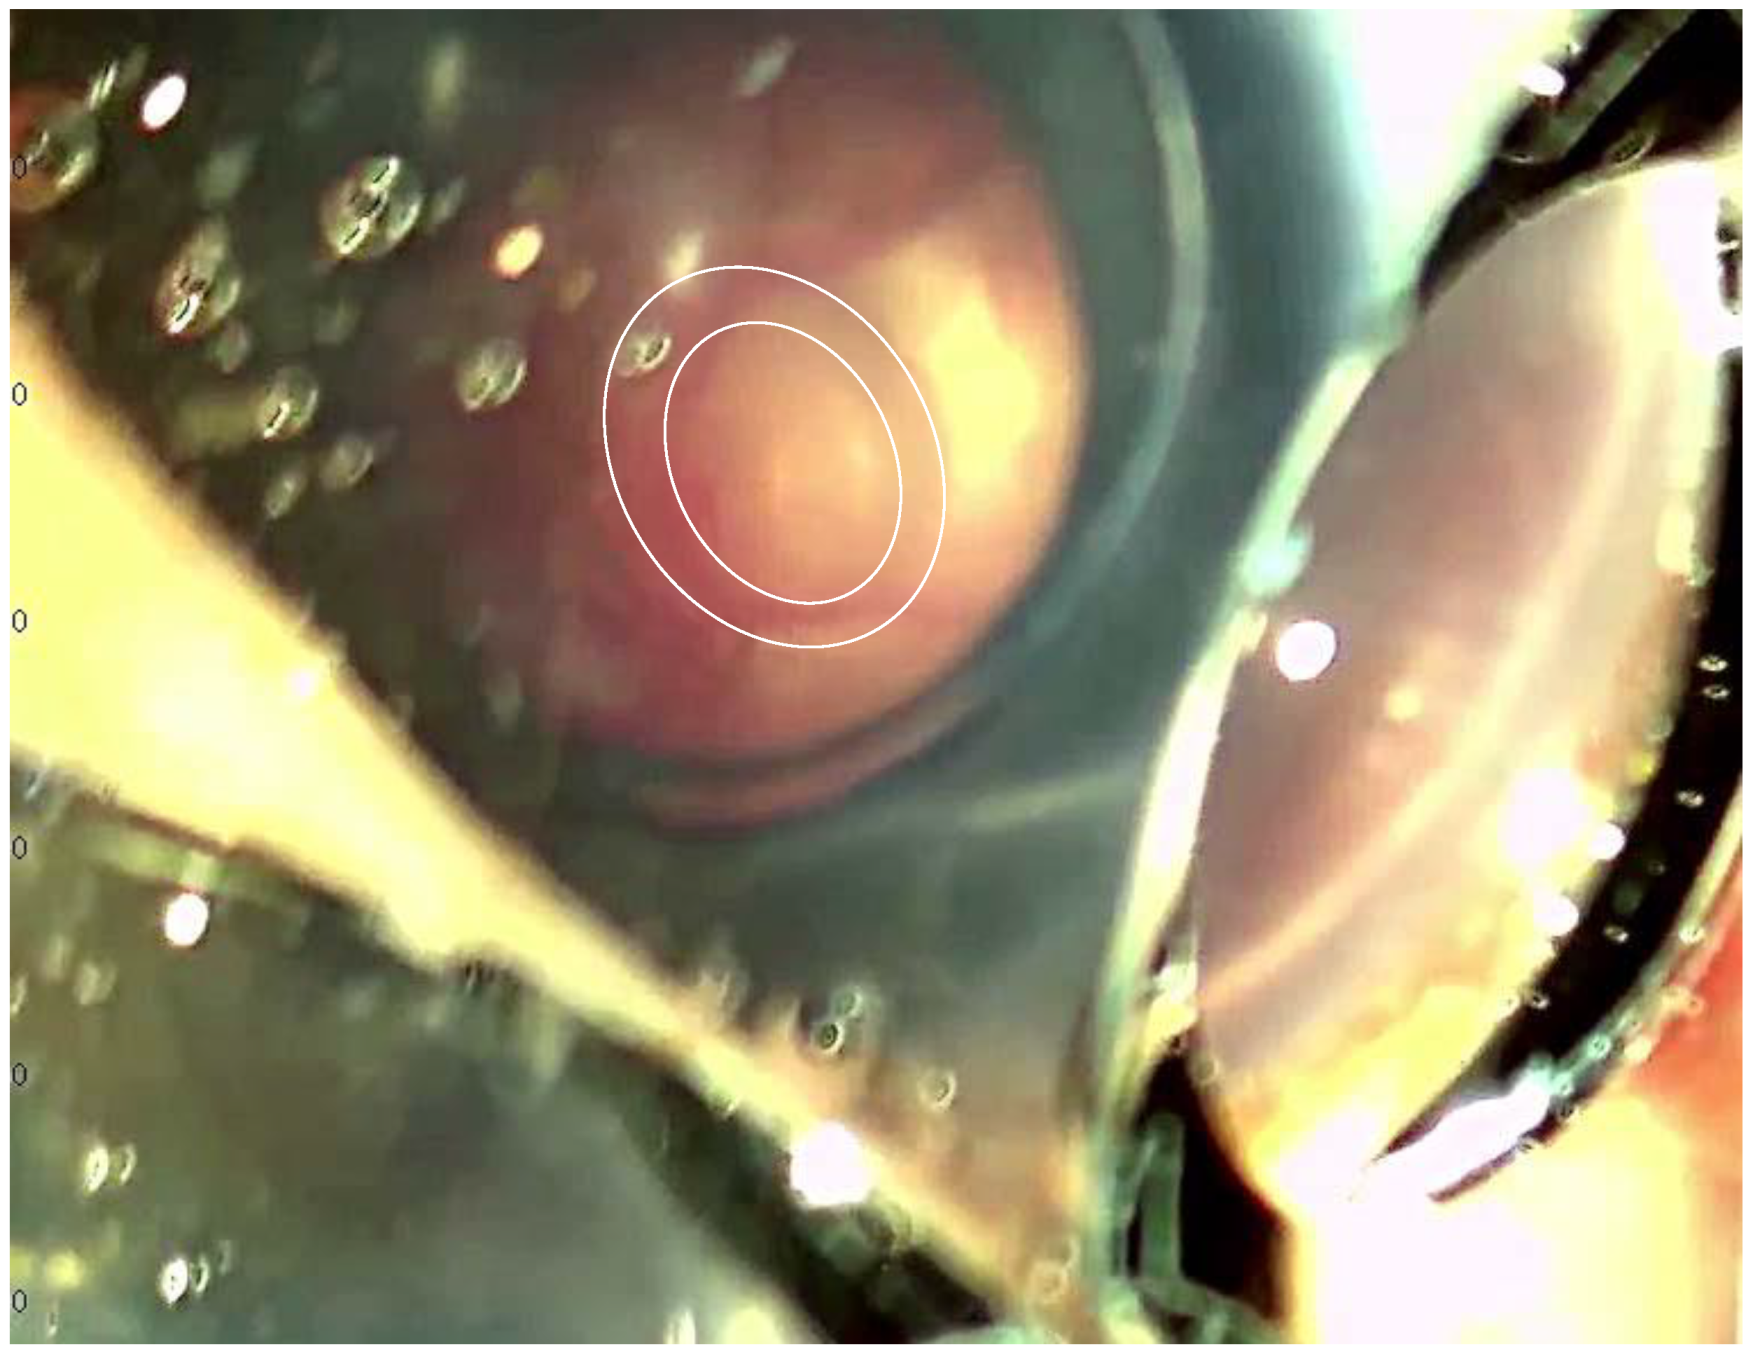

2. Case Report